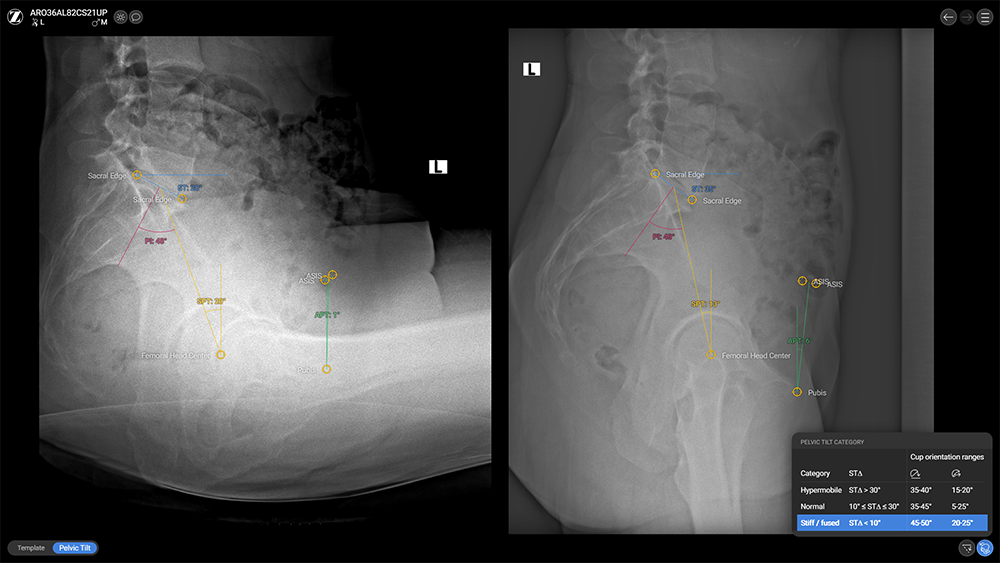

Pelvic Tilt Assessment

- Optional Spinopelvic Mobility Assessment tool: Requires a sitting and standing lateral X-ray with the AP X-ray

- Semi-automated (required landmarks need to be placed manually, subsequently values and angles are visualized automatically)

- Categorization of patient-specific spinopelvic mobility